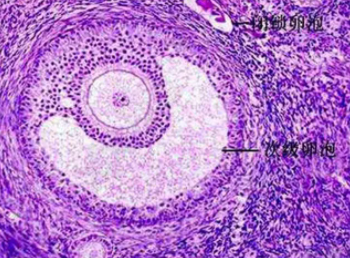

从初级卵泡成长至成熟卵泡可分成8个等级,且卵泡从第6级开始是需要注意的。第6级卵泡直径为5mm,卵泡在经过5天时间,长大到10mm,成为第7级卵泡;再经过5天的发育,到了第8级卵泡,直径是16mm;第8级的卵泡,就是成熟卵泡了。从第6级卵泡长大到第8级卵泡一共是10天时间,正好就是一个月经周期中的卵泡期。从一个卵泡成熟后到排出,其中还需要再经过2-3天,就会发育成20mm的卵泡,卵子就会排出。

卵泡成熟的标准